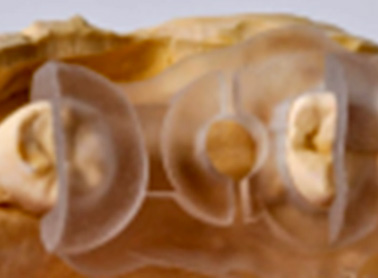

Trios3(POD)

Trios3(CART)

Oral Scanner